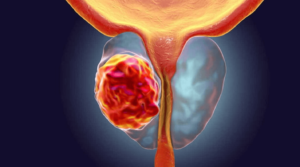

طریقہ کار سادہ ہے: اگر باقاعدہ صحت مند سرگرمیاں نہ ہوں تو نچلے جسم کے اعضاء میں خون کی گردش خراب ہوتی ہے، پیشاب کے مسائل شروع ہوتے ہیں، اور پروسٹیٹائٹس پیدا ہوتا ہے۔ ابتدائی مراحل میں اس مسئلے کی تشخیص مشکل ہوتی ہے، اور جب یہ سامنے آتا ہے تو اکثر جراحی مداخلت کی ضرورت پڑتی ہے۔ یورولوجی انسٹی ٹیوٹ سے لی گئی اس تصویر پر غور کریں:

48 سالہ مرد میں پروسٹیٹ کینسر۔ پروسٹیٹ کینسر صحت کی کمزوری سے دوچار مردوں میں موت کی سب سے بڑی وجہ (88% تک) ہے۔ یہ نچلے جسم کے اعضاء میں ناکافی خون کی گردش اور پروسٹیٹ میں سوزش کی وجہ سے ہوتا ہے۔ اس سے کینسر پیدا ہوتا ہے اور 1-2 سال کے اندر موت واقع ہو سکتی ہے۔